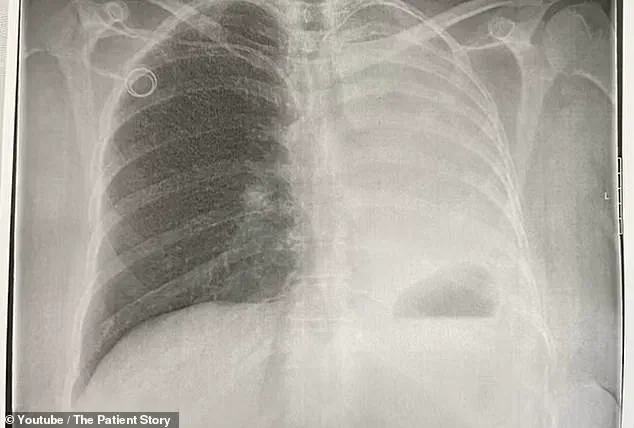

However, as the months passed, the disease progressed, spreading to her bones and one lung, leading to a stage four endometrial cancer diagnosis in 2022.

This approach was aimed at targeting the cancer that had already metastasized from her uterus to her lung.

Cancer is impossible to get out of the bone practically… and pretty much all you can do is slow it down.' The emotional weight of this revelation was compounded by the discovery that the cancer had also spread to one of her lungs.